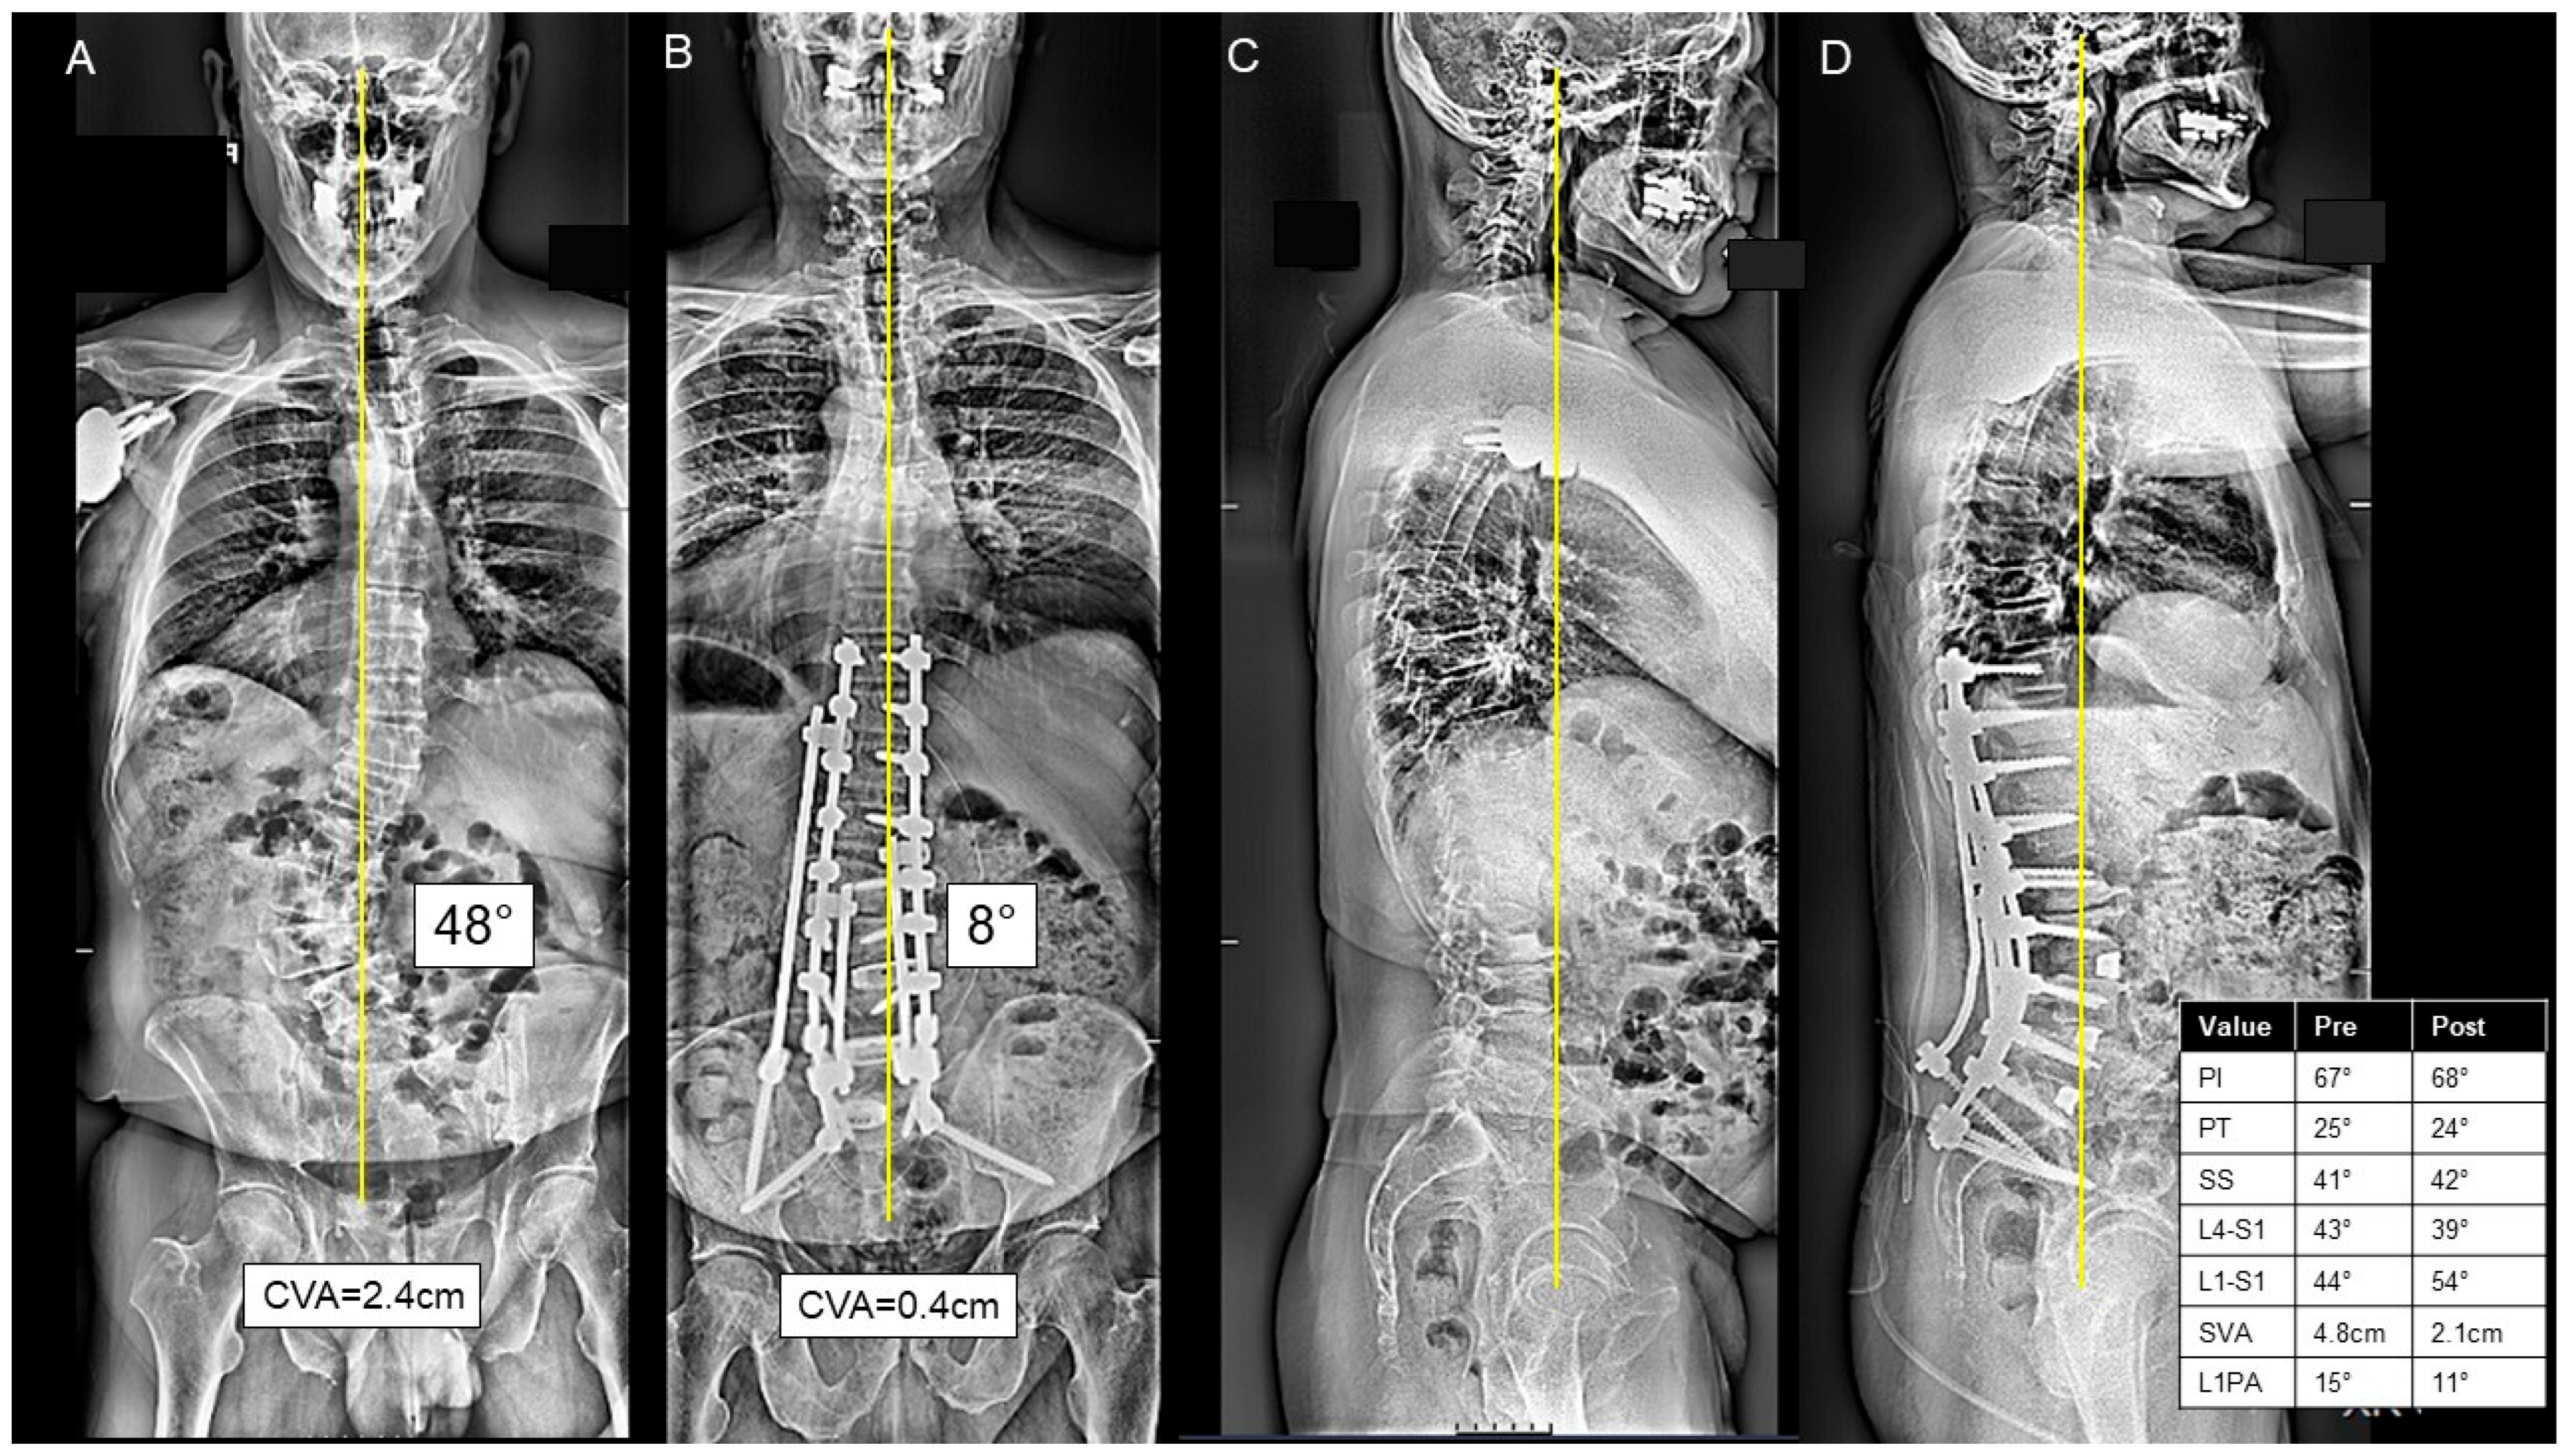

脊椎脊髄病学 第3版【電子版】 | 医書.jp。Spinal Cord Medicine, Third Edition –Comprehensive Evidence。Spinal Disorders: Fundamentals of Diagnosis and Treatment。裁断済の商品です。裁断の意味がわからない方は購入をご遠慮ください。中に目立った書き込みはありませんが、ページが曲がっている部分があります。写真でご確認ください。読む分には問題ありませんでした。裁断済のため傷汚れありとしております。佐川急便/日本郵便もしくは佐川急便/日本郵便で発送予定です。「脊椎脊髄病学 = PRINCIPLES OF SPINAL DISORDERS」岩崎 幹季定価: ¥ 15000#岩崎幹季 #岩崎_幹季 #本 #自然/医療・薬学・健康。Pathologies for T1-T12 (Thoracic Spine) - Spinal Backrack。医学書院/系統看護学講座 23冊 看護大学 教科書。誰にでもできる咬合採得。血液専門医テキスト 第4版。中国料理百科事典 定価158,000円。【クーポンコード未使用】year note 2026 第35版。日本人体解剖学 下 改訂20版